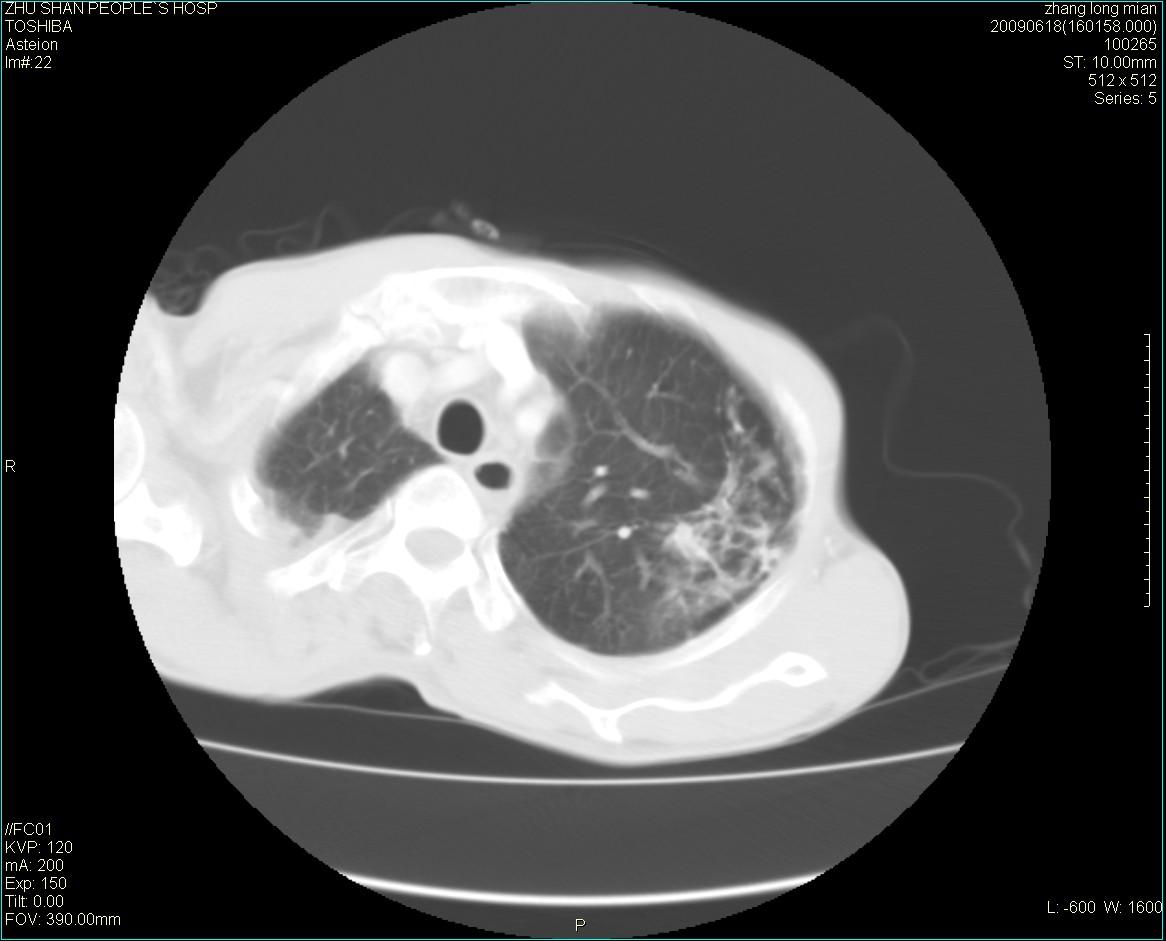

男性 65岁 胸片发现右下肺包块.诊断肺ca并纵隔转移没有问题吧!

两侧胸廓不对称,右侧呈塌陷改变,右肺萎缩。

增强见纵隔区气管隆突上下及左肺门区肿大淋巴结。左肺感染性病灶。

支持楼主意见。左上肺继发型肺结核.